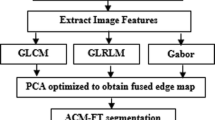

In this paper, we have proposed a new framework to use both PET and CT images simultaneously for tumor segmentation. Our method combines the strength of each imaging modality: the superior contrast of PET and the superior spatial resolution of CT. We formulate this problem as a Non-Local Active Contours (NL-AC) based-variational segmentation framework incorporating Belief Functions (BFs). The proposed method used all features issued from both modalities (CT and PET) as a descriptor to drive the NL-AC curve evolution. The new segmentation framework allows us to incorporate in the same framework heterogeneous knowledge in order to reduce the imprecision due to noise poor contrast, weak or missing boundaries of objects, inhomogeneities, etc. The proposed method was evaluated on relevant tumor segmentation problems. The results showed that our method can effectively make use of both PET and CT image information, yielding segmentation accuracy of 81.52% in Dice Similarity Coefficient (DSC) and the Average Symmetric Surface Distance (ASSD) of 1.2 ± 0.8 mm, which is 10% (resp., 16%) improvement compared to two state of art segmentation methods using the PET (resp., CT) images.